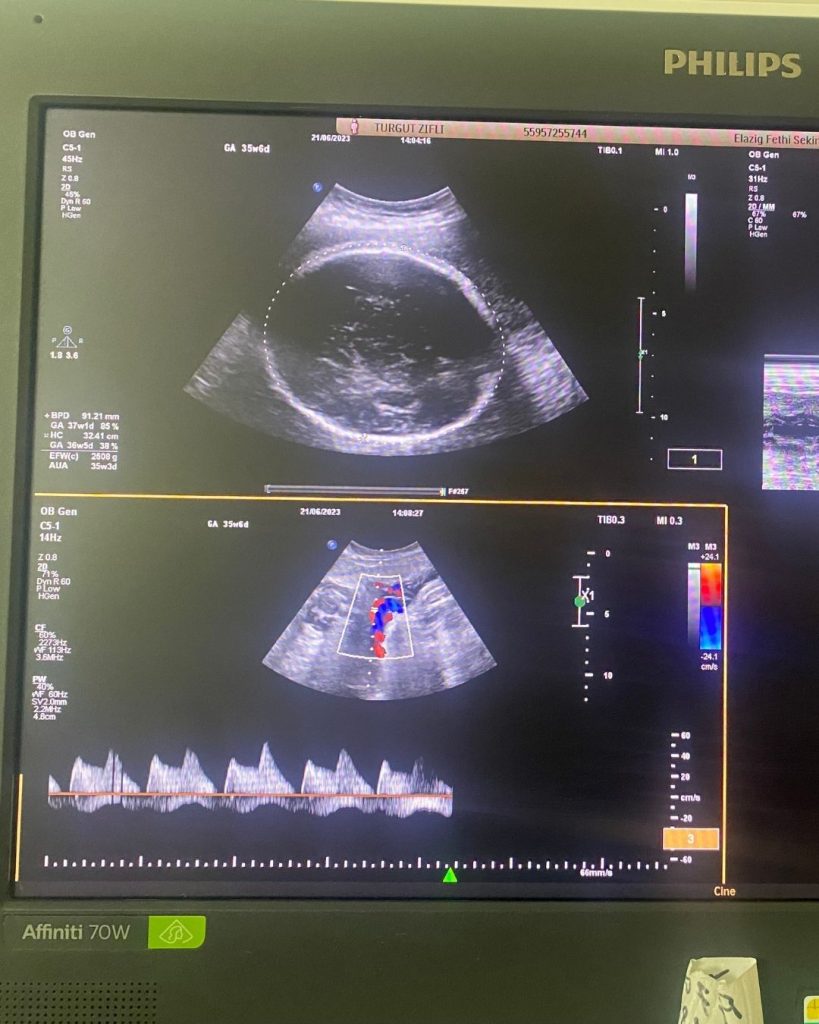

- Rutin Kontroller ve Testler: Anne kan testleri, idrar tahlilleri ve tansiyon ölçümleri ile annenin sağlığı izlenir. Bebeğin gelişimi ultrason ile takip edilir.

- Tarama Testleri (11-14. Hafta Tarama, Detaylı Ultrason): Bebeğin kromozomal anormallikler ve yapısal kusurlar açısından taranması. Özellikle 18-23. haftalar arası yapılan Detaylı Ultrason, bebeğin tüm organlarının incelenmesi açısından hayati öneme sahiptir. Bu hassas muayene için Op. Dr. Birsen Konukcu‘dan randevu alarak bebeğinizin gelişimini en doğru şekilde değerlendirebilirsiniz.

- Doğuma Hazırlık: Son haftalarda bebeğin doğum pozisyonu, plasentanın durumu ve doğum şekli planlanır. Fetal iyilik hali testleri (NST) ile bebeğin durumu yakından izlenir.